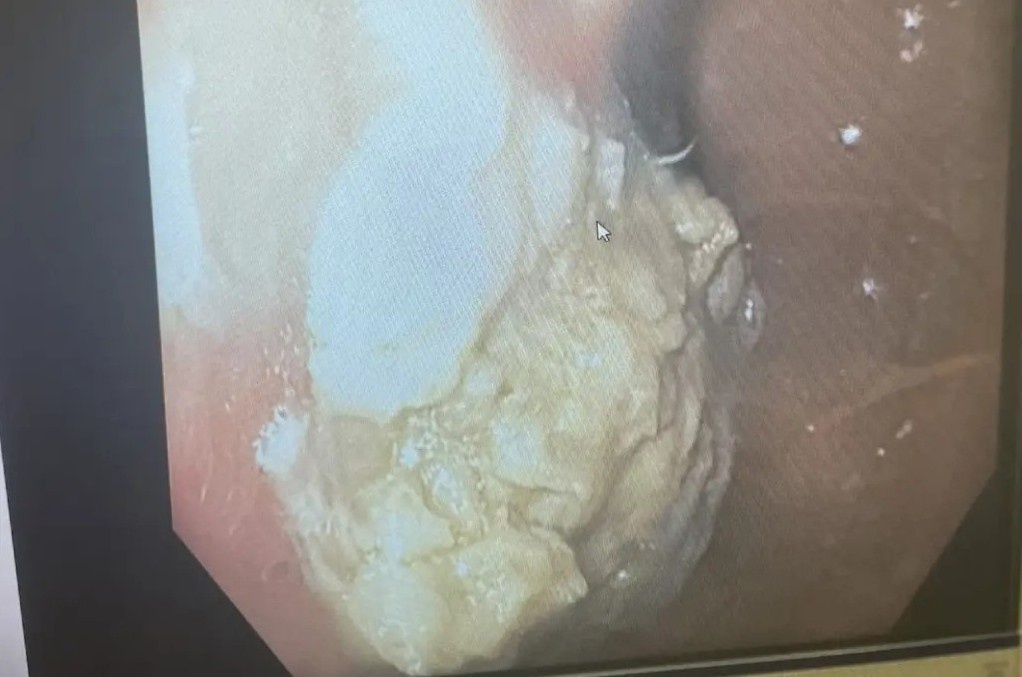

Nhập viện ở Thâm Quyến vào tháng 3, Xiaoling cao 1,65 m nhưng chỉ nặng 24,8 kg, nhẹ hơn trẻ tiểu học. Cô bị suy dinh dưỡng nặng, suy hô hấp, rối loạn điện giải, teo não và đã bất tỉnh. Sau hơn 20 ngày nằm tại khoa Hồi sức tích cực, nữ bệnh nhân đã qua đời.

Xiaoling được chẩn đoán mắc chứng chán ăn tâm thần, một chứng rối loạn ăn uống có tỷ lệ tử vong rất cao. Cha mẹ đã nhiều lần đưa Xiaoling đến bệnh viện nhưng cô chống cự quyết liệt.

Theo JHM, chứng chán ăn tâm thần ảnh hưởng đến phụ nữ nhiều hơn nam giới, thường bắt đầu trong những năm thiếu niên. Đây là tình trạng rối loạn ăn uống khi người bệnh hạn chế quá mức thức ăn đi kèm nỗi sợ hãi vô lý về tăng cân.

Các triệu chứng của bệnh bao gồm chán ăn, không thèm ăn nhưng cũng có thể cuồng ăn rồi tìm cách đào thải thức ăn ngay (gây nôn), tập thể dục quá mức, đầy bụng, táo bón, suy kiệt, rối loạn kinh nguyệt, không quan tâm đến tình dục, trầm cảm, tụt huyết áp, thân nhiệt, phù nề.